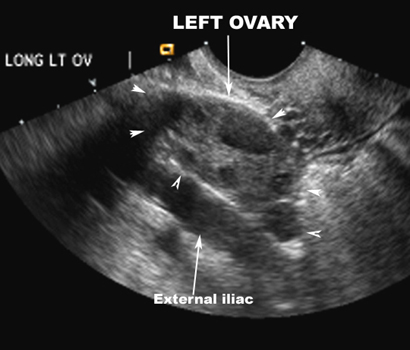

US Pelvis |

|